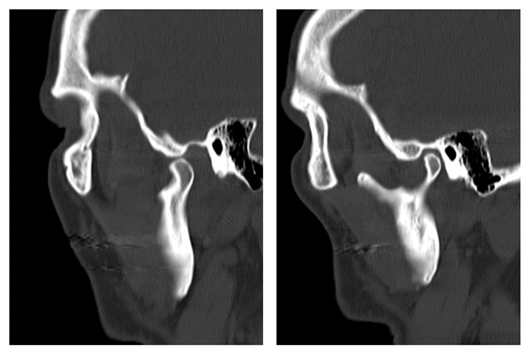

The dental team agreed with the initial diagnosis of a temporomandibular joint dislocation secondary to acute dystonic reaction. A maxillofacial CT confirmed the suspicion as shown in Figure 1 revealing an asymmetric forward translation of the right mandibular condyle which articulates with the articular tubercle of the right temporal bone. The Patient was advised to limit opening his mouth in order avoid pain and to prevent further displacement. The patient also reported a rash on his arms which started around the same time as the ADR. On physical examination, maculo-papular rash was observed on the patient’s upper extremities, most significantly from mid arm to hands for which he was started on oral prednisolone 20mg daily. Over the following 48 hours, there was a complete resolution of acute symptoms, the patient reported only minimal pain, his jaw range of motion was full, with minimal swelling and facial asymmetry and no clicks or other abnormality on passive and active motions of the temporomandibular joint. The patient’s started on Aripiprazole 5mg PO daily (titrated up to 10mg PO daily) and Benztropine 1mg PO bid after discontinuation of Haloperidol. He was later discharged to follow up at the outpatient psychiatry and dental clinic after ten days on the psychiatric inpatient unit with a compete resolution of all acute dystonic symptoms and no evidence of temporomandibular joint dysfunction.

Figure 1 CT image showing a displaced right temporomandibular joint compared to the intact left TMJ.